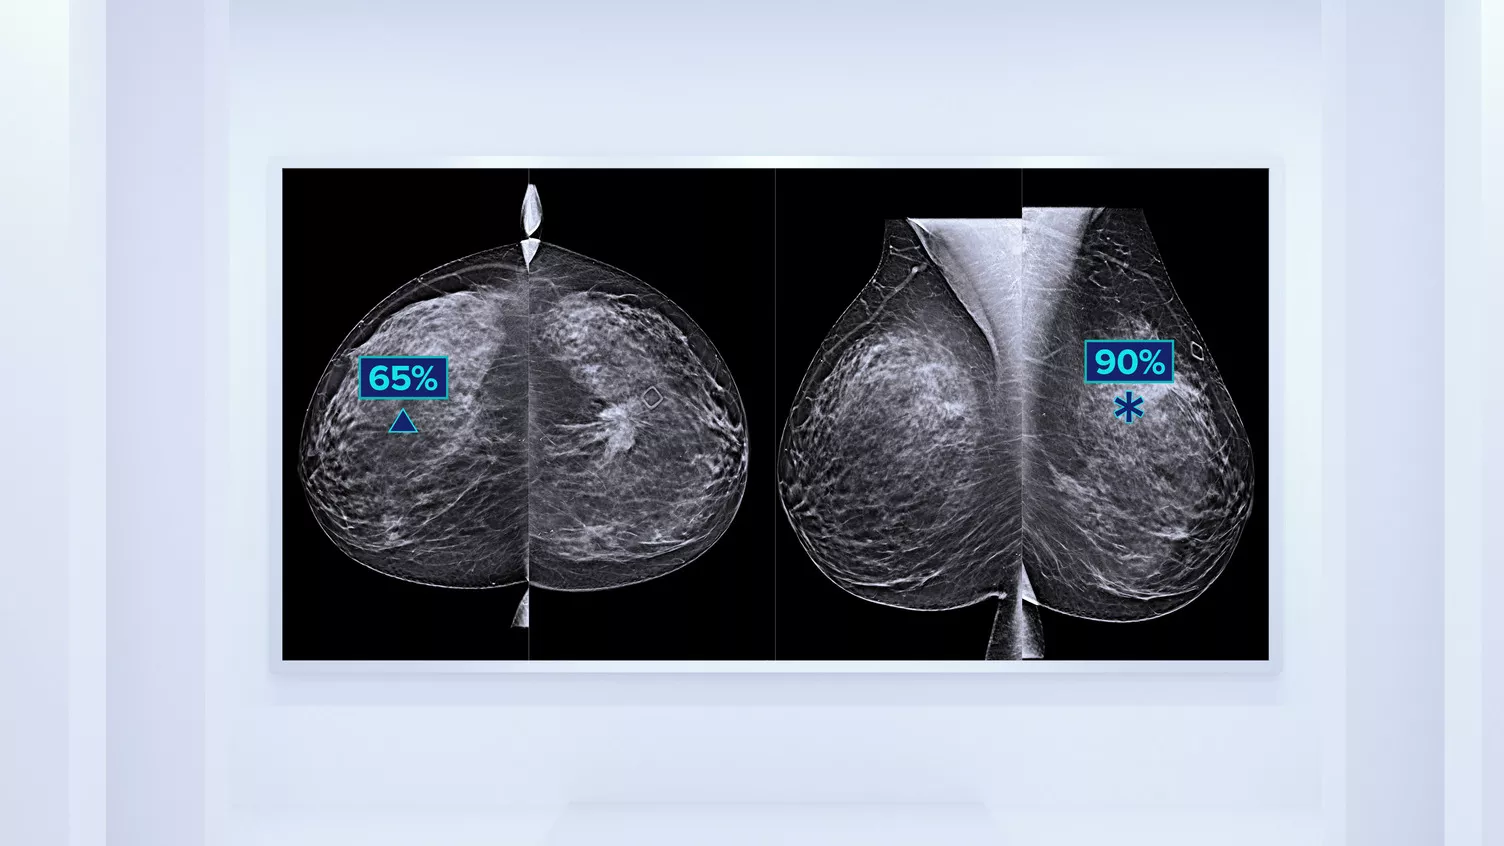

Sabemos que una densidad mamaria alta aumenta el riesgo de cáncer de mama en mujeres.1 Por tanto, es fundamental realizar un análisis preciso y sin sesgo. El software de la tecnología Quantra, basado en aprendizaje automático, analiza las imágenes 2D™ y de tomosíntesis para determinar la distribución y la textura del tejido parenquimatoso. Clasifica las mamas en cuatro categorías de composición mamaria de acuerdo con las directrices del Atlas BI-RADS (5.ª edición) del American College of Radiology (ACR).2

Además del volumen, el patrón y la textura del tejido fibroglandular pueden ser igualmente decisivos para la predicción mamográfica del riesgo de cáncer.3-5 Mediante el análisis y la clasificación de la textura y el patrón de la mama, nuestra tecnología puede ofrecer la información precisa que necesita para realizar una clasificación más fiable y completa y, de este modo, diseñar con seguridad una vía de detección específica para cada paciente.

El algoritmo de aprendizaje automático objetivo asigna una categoría de densidad de mama de acuerdo con los patrones y la textura del tejido de la mama.

* Las clasificaciones se basan en las categorías BI-RADS del ACR, de acuerdo con las directrices revisadas publicadas en el Atlas BI-RADS (5.ª edición) del American College of Radiation (ACR). Estas directrices tienen en cuenta el patrón y la textura, y no solo el volumen, a la hora de determinar la densidad.